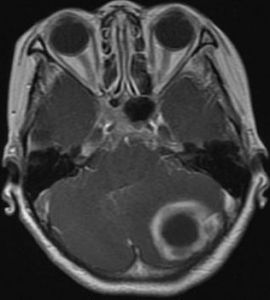

8、腦CT 是目前診斷腦膿腫的主要方法,適用於各種部位的腦膿腫。由於腦CT檢查方便、有效,可準確顯示膿腫的大小、部位和數目,故已成為診斷腦膿腫的首選和重要方法。腦膿腫的典型CT表現為:邊界清楚或不楚的低密度灶(0~15HU),靜脈注射造影劑後,膿腫周邊呈均勻環狀高密度增強(30~70HU),膿腫中央密度始終不變,膿腫附近腦組織可有低密度水腫帶,腦室系統可受壓、推移等。如膿腫接近腦室,可引起腦室管膜增強征。少數腦膿腫的增強環不均勻,或有結節狀。可是腦CT顯示的"環征"並非腦膿腫特也可見於神經膠質母細胞瘤、轉移癌,囊性膠質細胞瘤,腦梗塞和腦內血腫等。因此應結合病史注意鑑別。一般腦膿腫有感染史,CT顯示的環較均勻,伴有室管膜增強,還是容易識別。在腦炎晚期,CT也可顯示"環征",此乃因腦炎引起血腦屏障改變,血管周圍炎性細胞浸潤和新生血管形成等所致,因此腦炎的"環征"與膿腫包膜的"環征"在本質上不同。兩者的區分,除結合發病時間外,可採用延遲CT檢查法,即在靜脈注射造影劑30分鐘後掃描,腦炎原來低密度中央區也變成高密度,但膿腫中央區密度不變。由於類固醇激素有抑制炎症反應和成纖維增生、新生血管形成的作用,從而影響膿腫包膜形成,因此,對可疑病人應停用激素後重複CT檢查。

9、磁共振成像(MRI)是近年套用於臨床的新檢查方法。在腦炎期病灶呈邊緣不清的高信號改變,中心壞死區為低信號改變,T2(橫弛豫時間)延長,周邊腦水腫也呈高信號變化,灰白質對比度消失,T1(縱弛豫時間)和T2也延長。腦炎晚期的病灶中央低信號區擴大,IR(反向復原)成像示中央區仍為低強度。包膜形成期的中央區低信號,T1延長,但在長TR(重複時間)成象時原低信號變成較腦脊液高的高信號。包膜則為邊界清楚的高信號環。鄰近腦灰白質對比度恢復正常,但T1,T2仍輕度延長。因此MRI顯示早期腦壞死和水腫比CT敏感,區分膿液與水腫能力比CT強,但在確定包膜形成,區分炎症與水腫不及CT敏感。

5、電子計算機斷層腦掃描(CT)及磁共振成像檢查(MRI):自從CT及MRI用於臨床,對顱內疾患,尤其占位病變的診斷有了重大突破。CT可顯示腦膿腫周圍高密度環形帶和中心部的低密度改變。MRI對膿腫部位、大小、形態顯示的圖像信號更準確。由於MRI不受骨偽影的影響,對幕下病變檢查的準確率優於CT。CT和MRI能精確地顯示多發性和多房性腦膿腫及膿腫周圍組織情況。